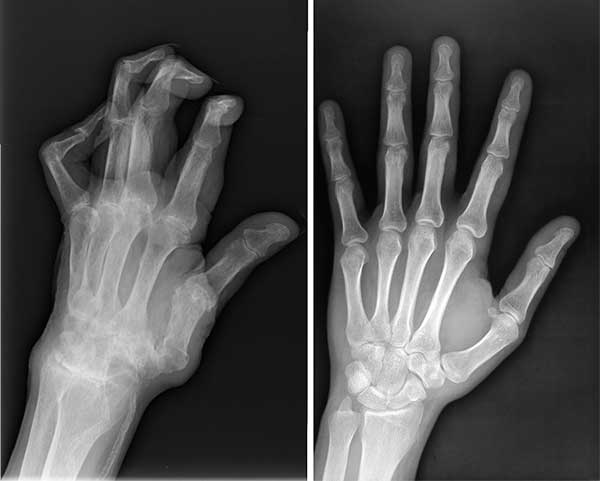

Saya bukan satu-satunya yang diselamatkan oleh produk ajaib ini. Suami saya juga menderita sakit di lengannya dalam waktu yang lama. Jari-jarinya mengalami cedera parah dan akhirnya didiagnosis menderita radang sendi. Saya memutuskan untuk membeli Invanil untuknya. Kami berdua mulai mengonsumsi bubuk ini bersama-sama, dan ternyata produk ini berhasil menyembuhkan kami berdua.

Rontgen suami sebelum dan sesudah mengonsumsi Invanil

Keadaan tangan suami saya sebelum dan sesudah mengonsumsi Invanil